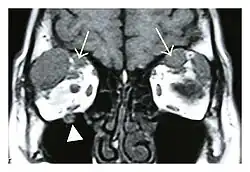

Mass lesion around the right optic disc in a 44-year-old man with IgG4-related ophthalmic disease and a serum IgG4 of 599 mg/dL.[1] (T2-weighted MRI) | |

The extent of inflammation that can occur in IgG4-ROD is well demonstrated on magnetic resonance imaging (MRI).